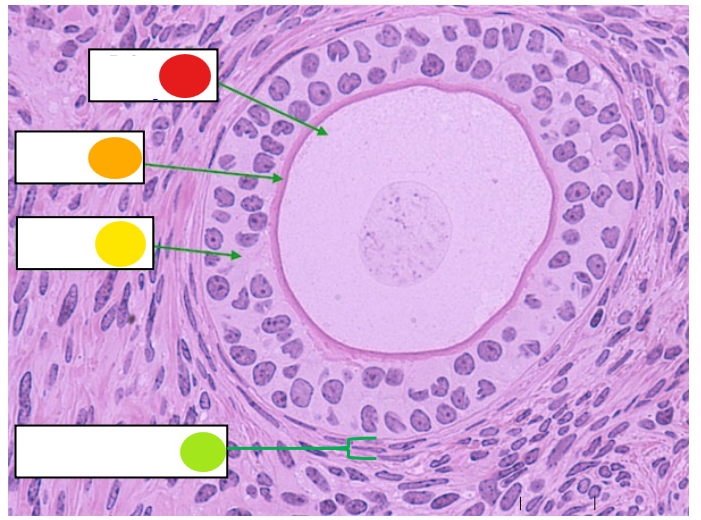

red

granulosa cells

orange

primary oocyte

what is this

primary follicle